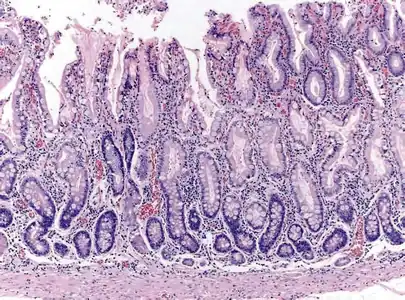

Histopathology of fundic mucosa with atrophy. H&E 10x; square 20x. Fundic-corporal gastric mucosa with extensive loss of gastric glands, partially replaced by pseudo-pyloric metaplasia.